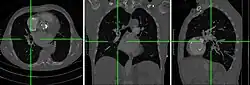

Bei der MPR werden aus diesen transversalen Schnitten frontale, sagittale, schräge oder kurvenförmige Schnitte errechnet und dargestellt, um dem Betrachter bei der anatomischen Orientierung zu helfen. Schräge (oblique) Schnitte sind beispielsweise in der Herzbildgebung hilfreich (Vierkammerblick, Kurzachsenschnitte), kurvenförmige Rekonstruktionen entlang selbst mehrfach gebogen verlaufender Strukturen für die Darstellung von Gefäßen (etwa den Koronararterien) oder den Harnleitern.